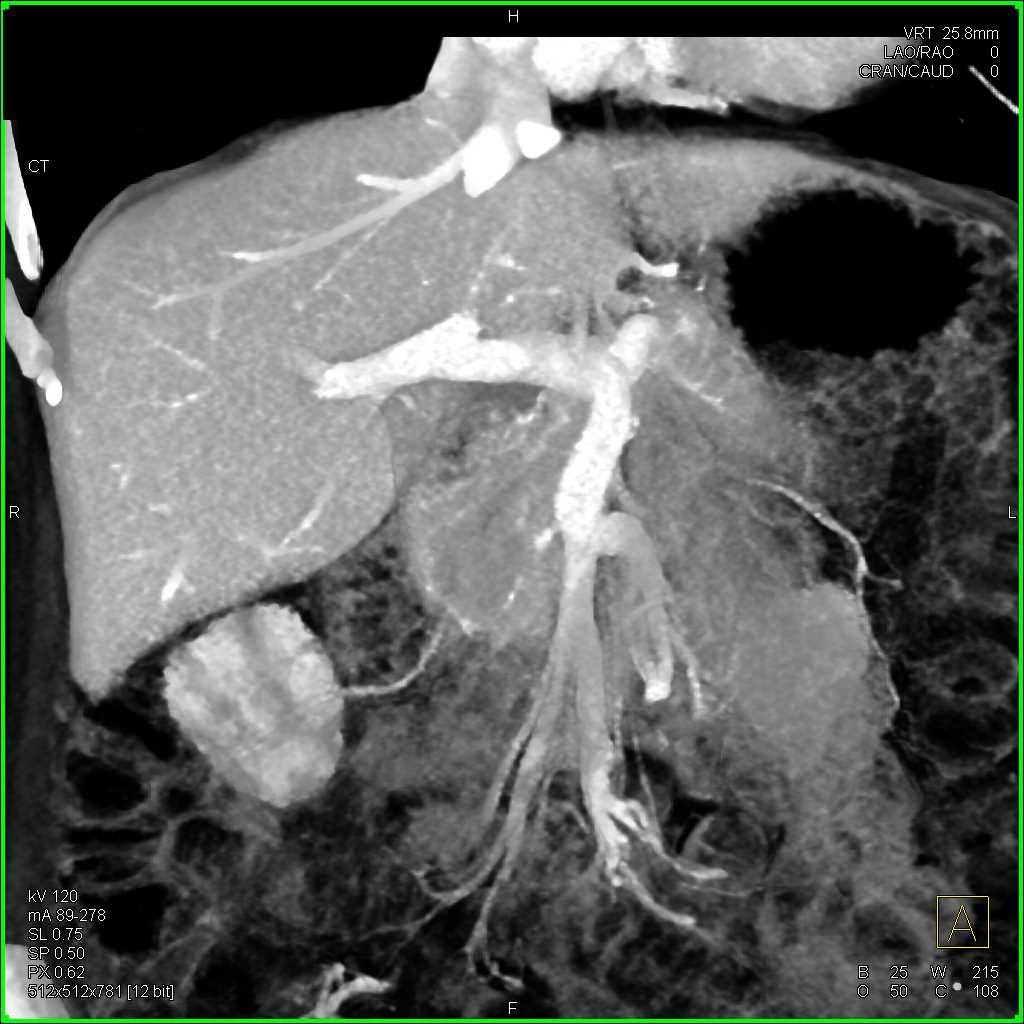

Intraductal Papillary Mucinous Neoplasm (IPMN) with High Grade Dysplasia